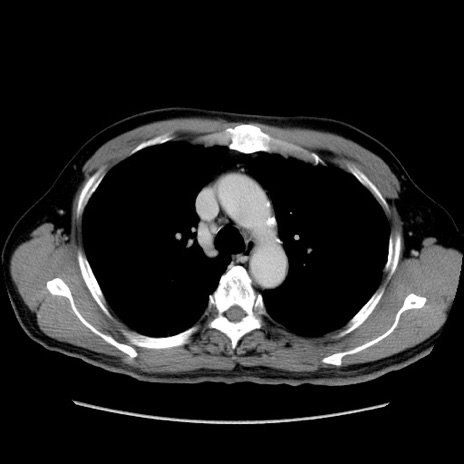

症例34(横断像)

【症例】60歳代 男性

【主訴】右鼠径部膨隆

【現病歴】1年程前より右鼠径部膨隆あり。自己にて還納可能だったため放置していた。3時間前より右鼠径部の脱出を認め、還納困難となり受診。

【既往歴】高血圧

【身体所見】右鼠径部に小児頭大の膨隆あり。弾性硬であり、用手還納は困難。左鼠径部にも膨隆を認める。脱出はなし。

【データ】WBC 15500、CRP 測定なし